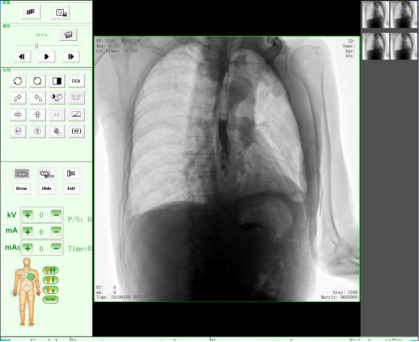

动态DR17*17英寸非晶硅动态平板探测器,透视像素达200万,可实时显示大幅面高清拍摄视野。适用于全身各部位摄影,包括常规摄影,如胸片、颈椎、腰椎、腹部、头颅、四肢等,以及特殊摄影。

适用于全身各部位的透视检查及辅助治疗,如隐匿性肋骨骨折、胸透检查、骨折复位、小儿肠套叠空气灌肠等。同时具备多种帧率透视模式,影像更加流畅、准确。